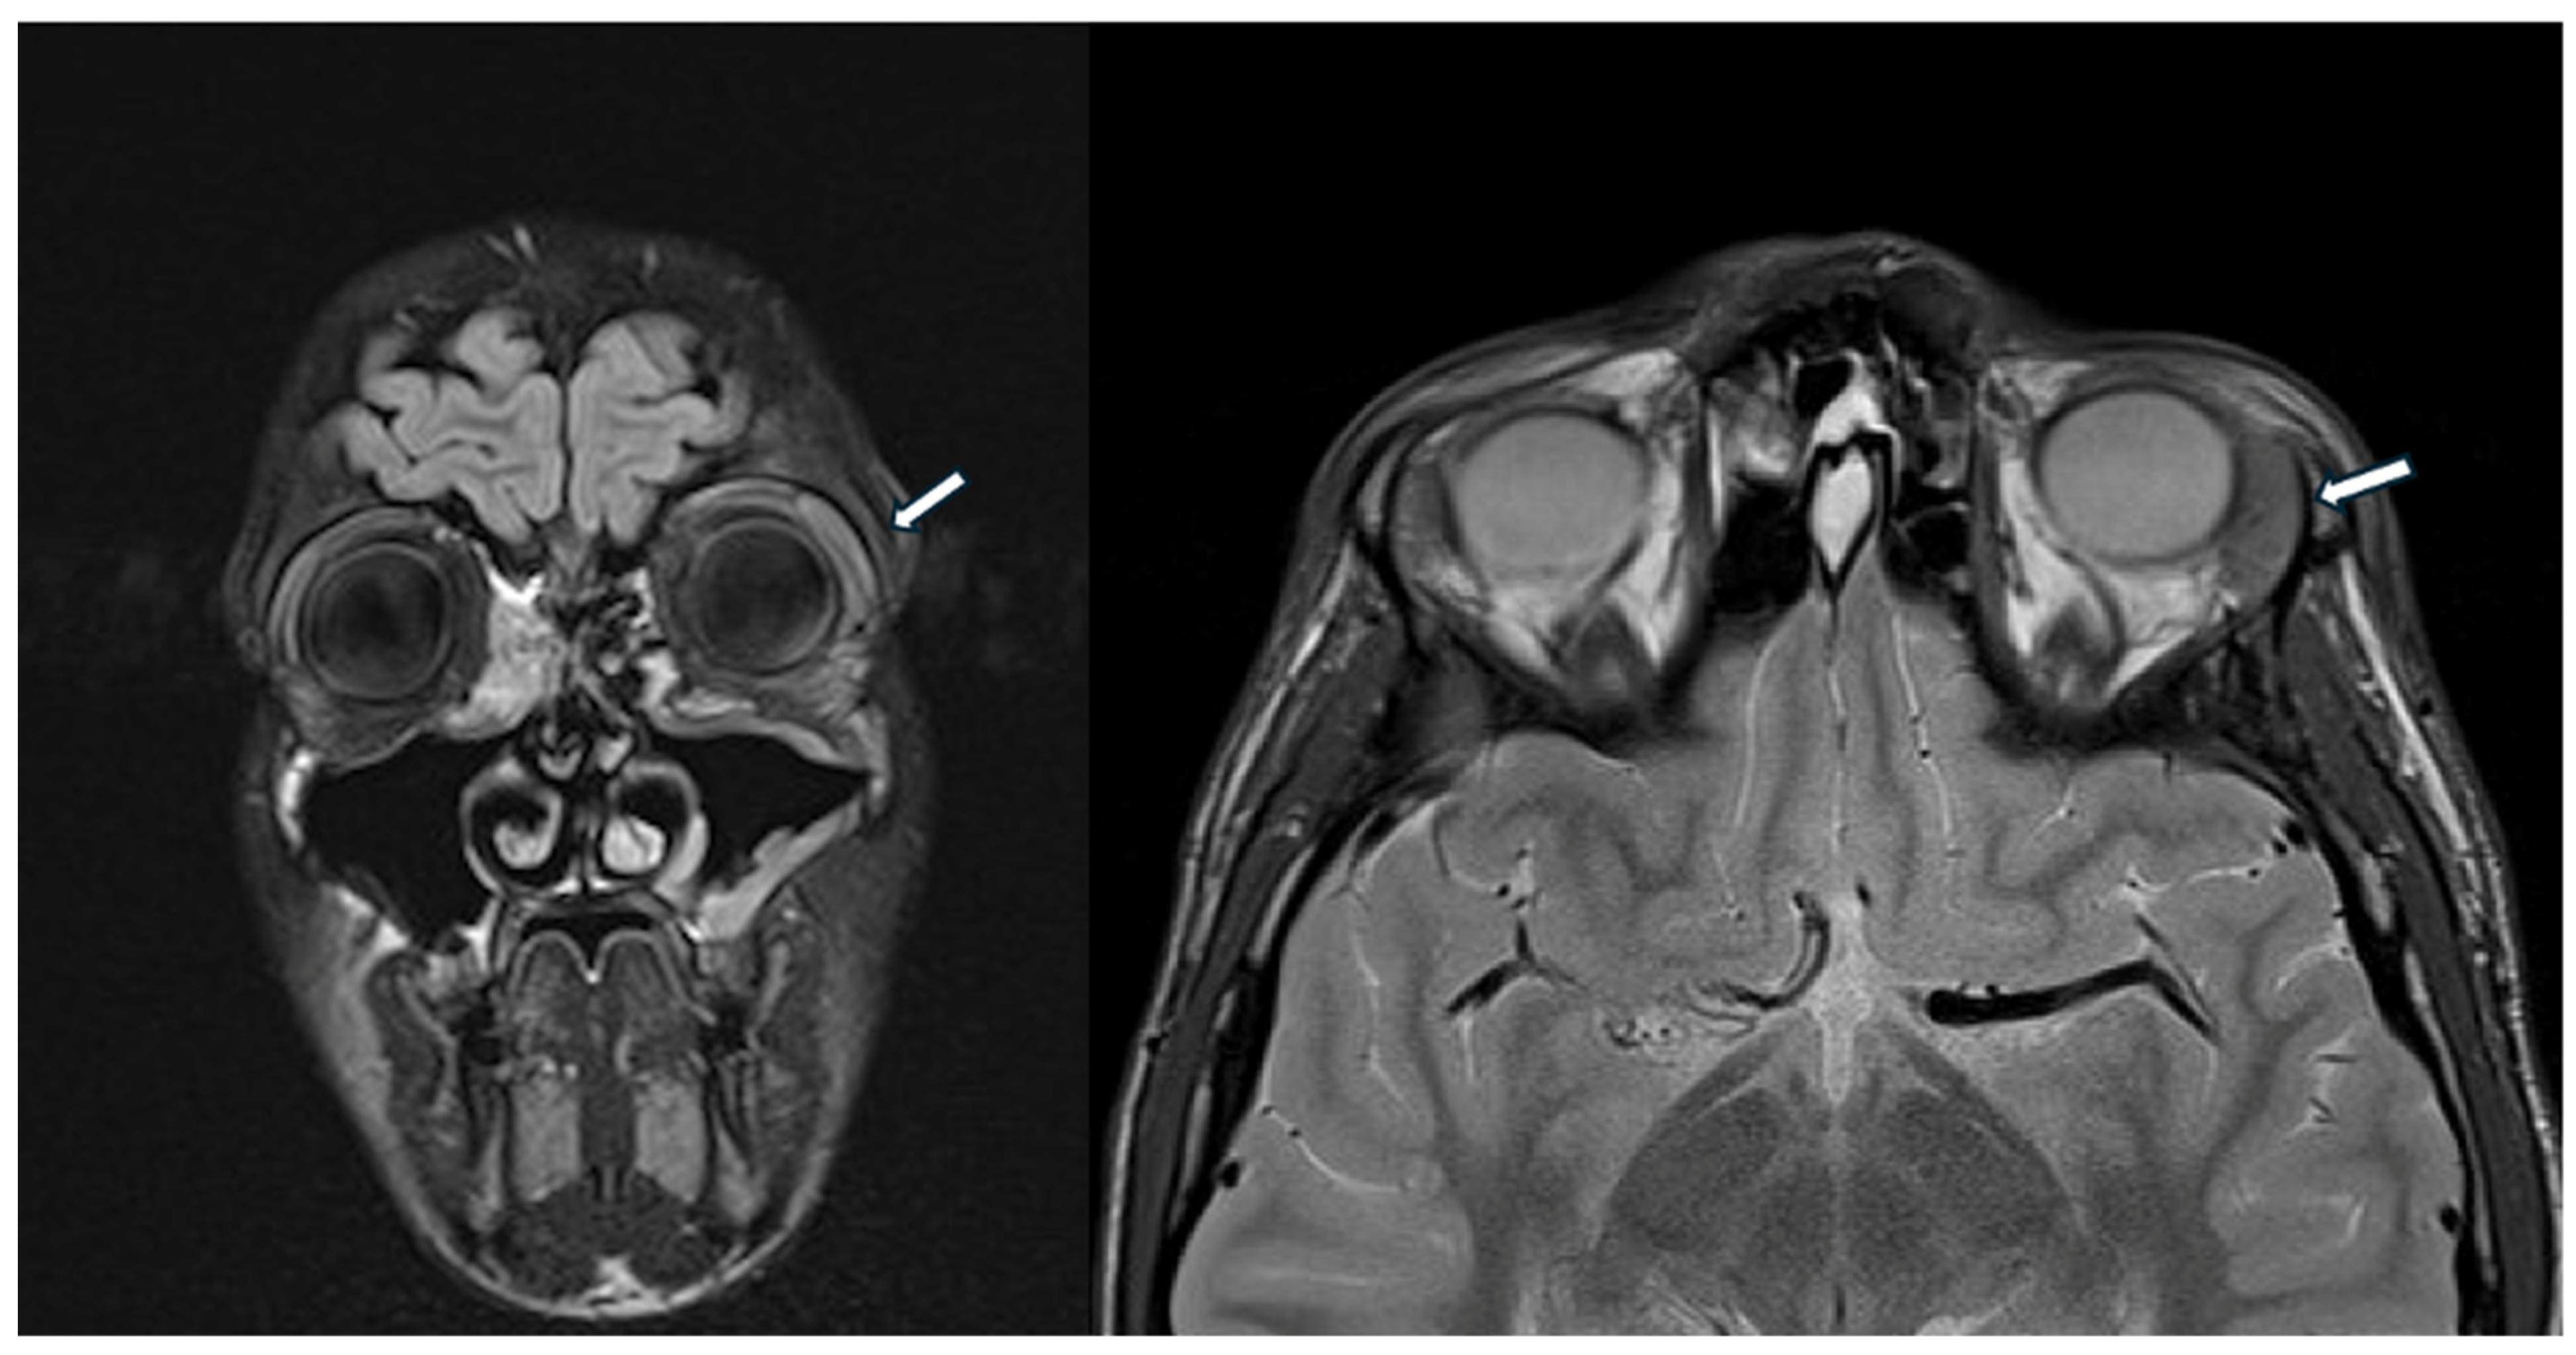

A previously healthy 14-year-old male was referred to our pediatric rheumatology outpatient clinic for recurrent dacryoadenitis. This condition had been diagnosed three years earlier at a local ophthalmological center, where the patient presented with bulbar conjunctival hyperemia and eyeball pain and underwent bulbar ultrasound, optical coherence tomography (OCT), and cranial CT scan, revealing peripalpebral soft tissue swelling on the left portion of the eye. A beneficial treatment with oral and topical antibiotic therapy, along with topical corticosteroids, was initially prescribed. Additionally, corrective lenses have been prescribed for simple hypermetropic astigmatism. However, due to the recurrence of inflammatory episodes coinciding with the tapering of corticosteroids, an orbital MRI was performed, revealing an enlarged left lacrimal gland and minimal peribulbar fluid (Figure 3).

Figure 3.

The head MRI shows enlarged left lacrimal gland (white arrow) and minimal peribulbar fluid.

Routine blood exams provided uninformative results, except for increased IgG4 levels (2970 mg/L, nv < 1350 mg/L). Suspecting systemic IgG4-RD, the boy was referred to our pediatric rheumatology clinic.